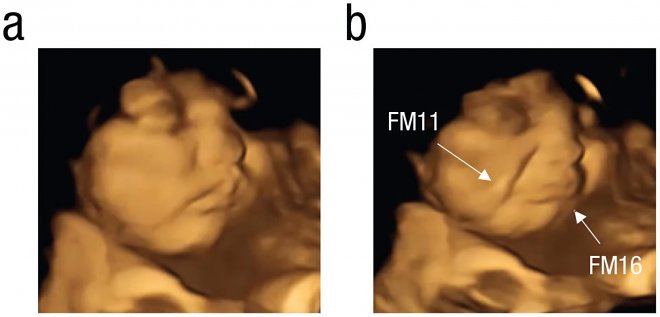

Реакция плода на вкус моркови

Женщинам давали пилюли с порошком капусты кейл и морковки. Первый отличается горьким вкусом, второй воспринимается как сладкий, хотя там нет сахара. В результате сканер зафиксировал отчетливую реакцию плода – их личики морщились или улыбались в ответ на горький или сладкий вкус, соответственно. Данные были проверены на контрольной группе, которая не получала никаких особенных вкусовых веществ.